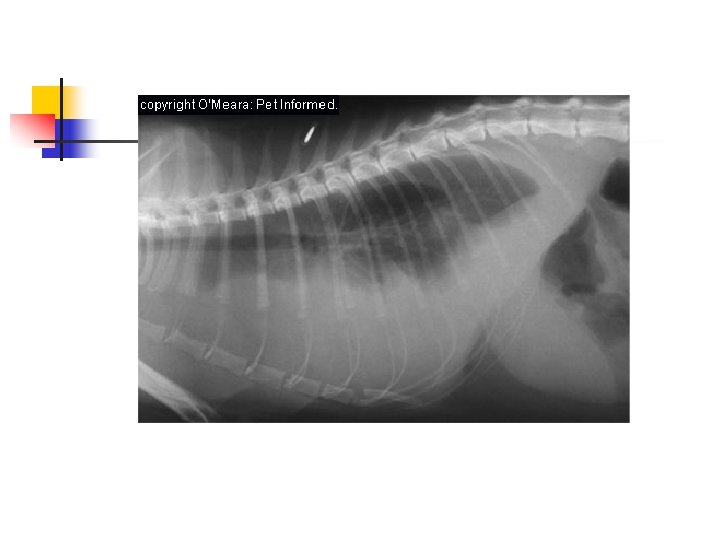

Thoracentesis n n n Pleural effusion may be bilateral or unilateral. Radiographs help determine the extent and location. Usually place in sternal recumbency. Aseptic prep. Sterile needle, catheter inserted next to cranial surface of the rib to prevent risk of penetrating the vessel on the caudal border of the rib.